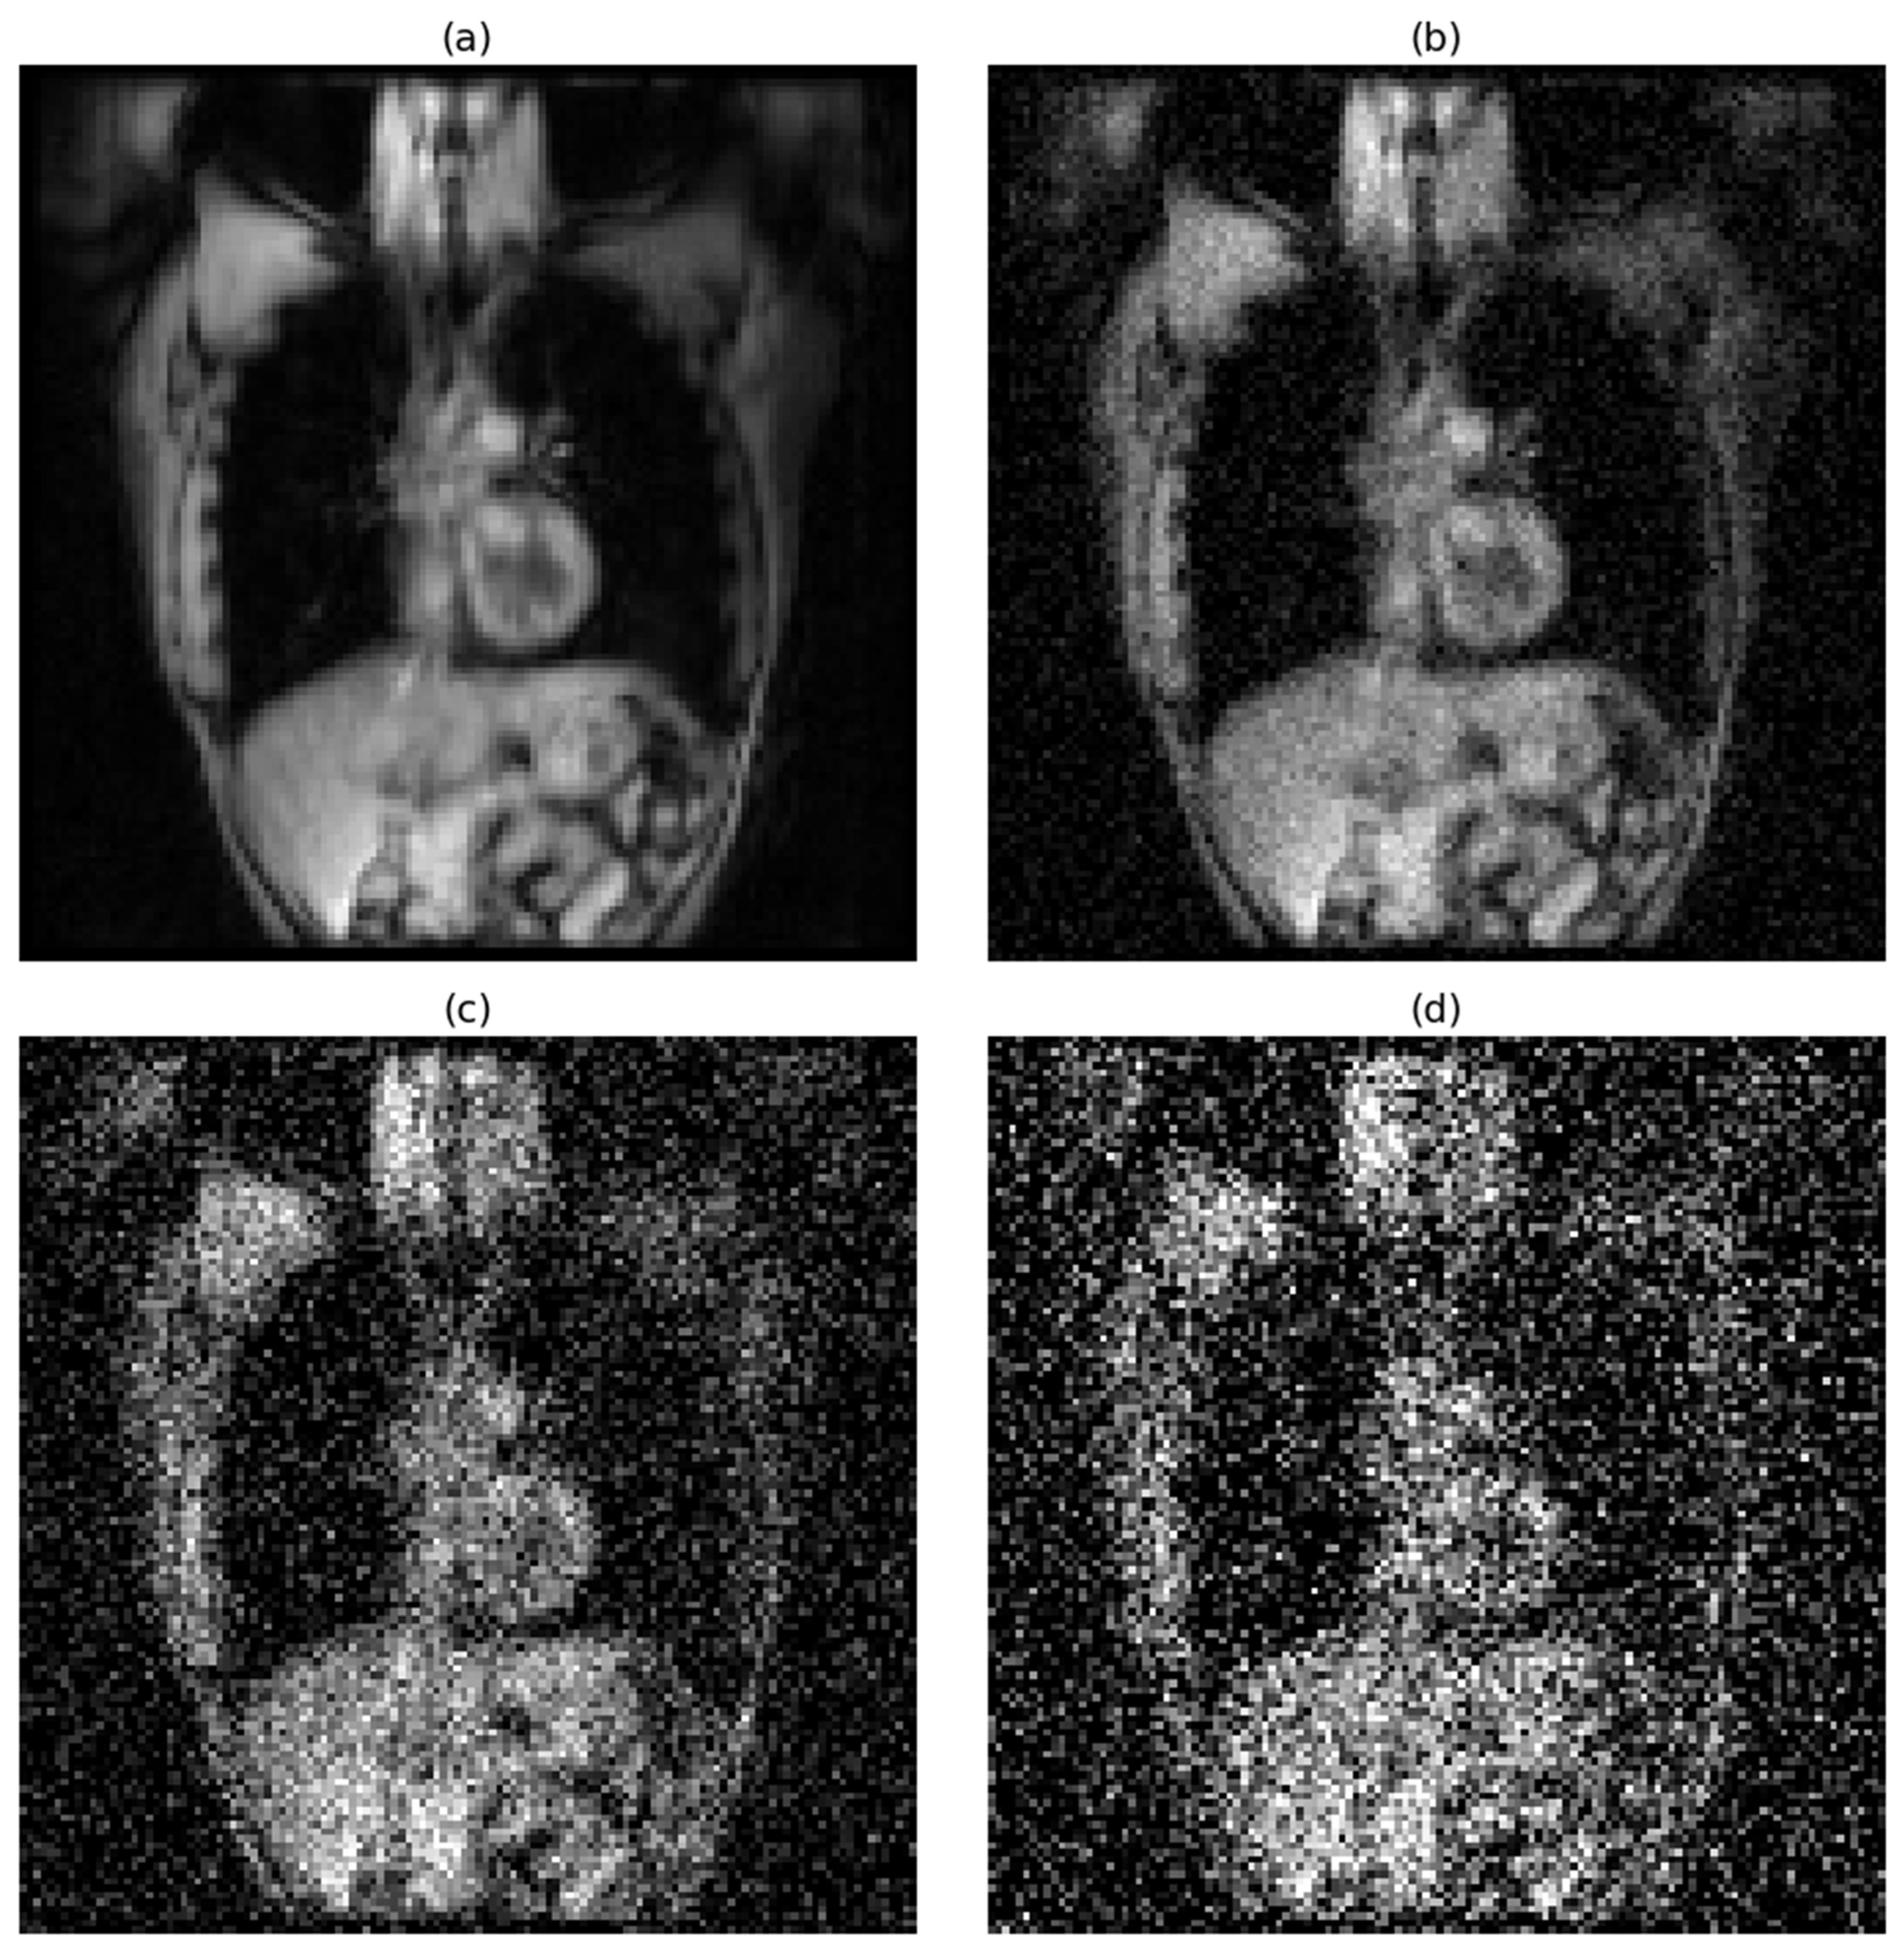

For proton MRI, the signal-to-noise ratio followed a similar degradation pattern under the same noise conditions. Under noise-free conditions, the average SNR for proton MRI was 59, representing good image quality, though lower than that observed in hyperpolarized gas MRI. When low-level Gaussian noise (std = 0.05) was introduced, the SNR decreased to 16.23. Medium noise (std = 0.15) further reduced the SNR to 6.84, while high noise (std = 0.25) resulted in an SNR of 3.86. Notably, the high noise condition for proton MRI fell below the Rose criterion threshold of 5, indicating that reliable object detection becomes significantly more challenging under these conditions. This systematic degradation in both imaging modalities provided a comprehensive framework for evaluating model robustness across varying image quality scenarios commonly encountered in clinical practice.

The effects of progressive noise addition on image quality are visually demonstrated in Figure 1 for hyperpolarized gas MRI and Figure 2 for proton MRI.

Figure 2. Progressive degradation of proton MRI image quality under varying noise conditions. Representative coronal slice demonstrating the impact of increasing Gaussian noise levels: (a) original image without noise (SNR = 59), (b) low-level noise with a standard deviation of 0.05 (SNR = 16.23), (c) medium-level noise with a standard deviation of 0.15 (SNR = 6.84), and (d) high-level noise with a standard deviation of 0.25 (SNR = 3.86).